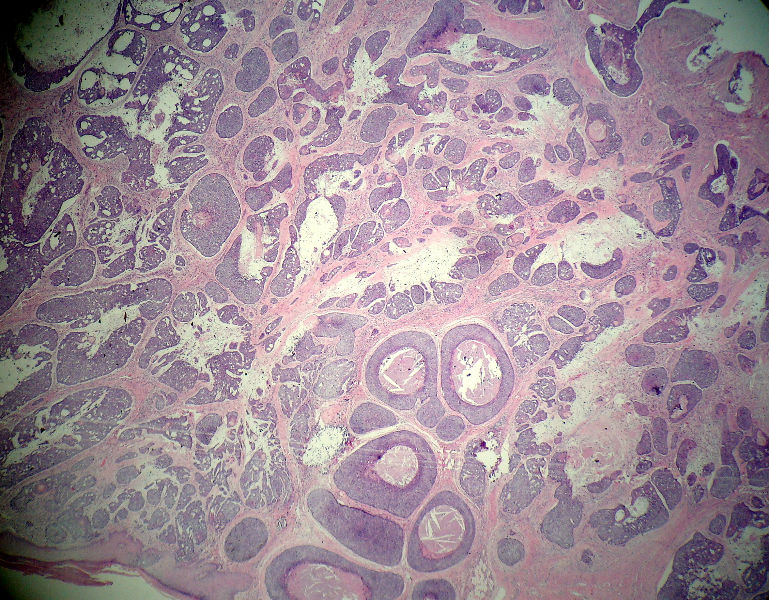

后枕部肿物

男,49岁,后枕部肿物3年,偶有破溃出血。

大体:皮肤半球形隆起,大小约2.3×2厘米,高出皮表0.8厘米,切面灰白,质地细腻。

似乎既有腺样结构,也有角化珠形成,还有细胞团内的粉刺样坏死。

有坏死、囊肿、钙化及胆固醇样裂隙等结构

考虑外毛根鞘肿瘤,局部癌变。

大部分区域看着象基底细胞癌,后面几张(11-14)看着象是鳞癌。综合考虑基底细胞样鳞癌。